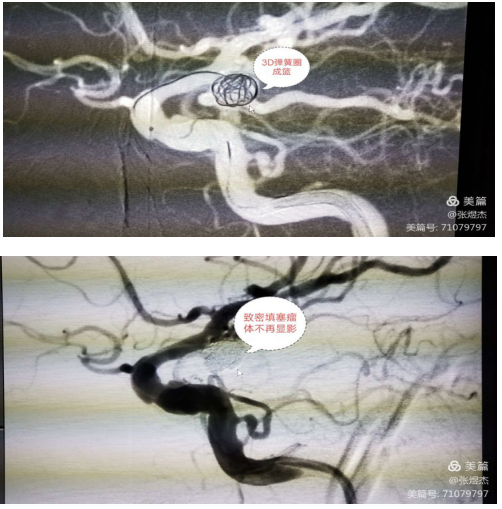

该患者脑动脉瘤位于颈内动脉后交通段,可以看见后交通动脉从瘤颈部发出,为手术带来了难度。

先用三维弹簧圈成篮后再逐步向内填塞,最终致密填塞后,造影瘤体不显影,血流不再进入,解除了动脉瘤再破裂的风险。